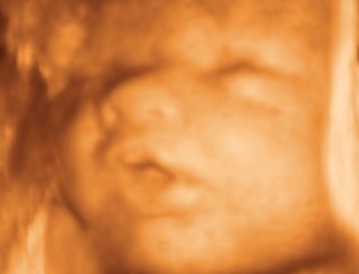

Cara 3

Cara